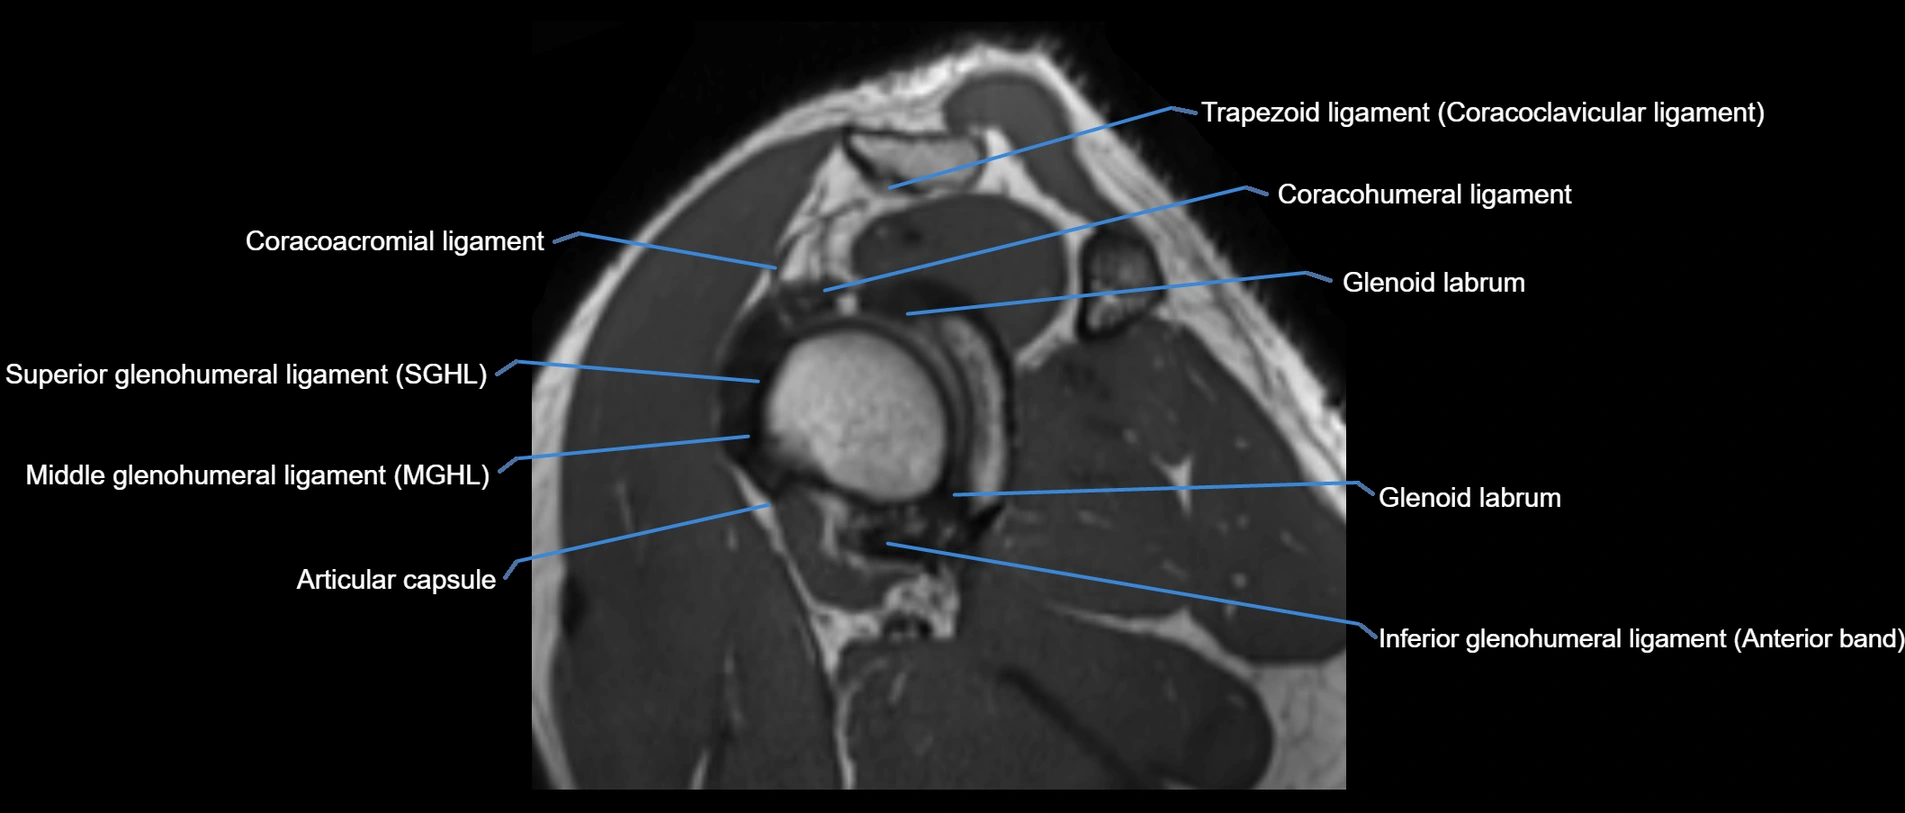

MRI images

image